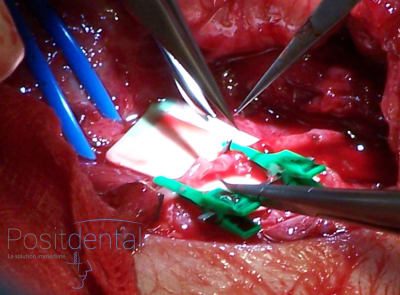

> patiente en fin d'intervention

> > patiente en fin d'intervention

mais serieusement, la c'était vraiment fini ? elle est allée en salle de réveil comme ca ?? :

non, comme ça!

donc elle est bien allee en salle de reveil non suturee... vache...

la sincèrement c est quand meme pas terrible... je veux bien rigoler un peu mais ca c est pas acceptable.

a moins que pas suturer ce soit aussi pour simplifier...

> il a la tremblote le chirurgien qui suture au passage...

Pour faire de la micro chirurgie ?